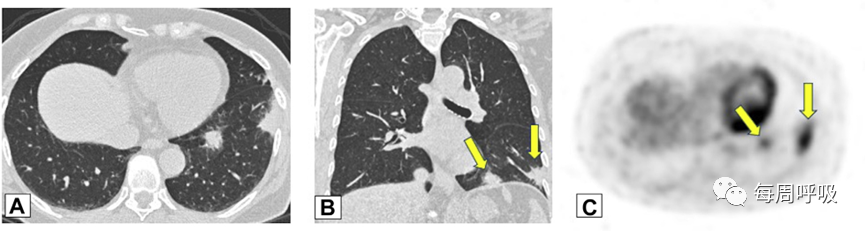

范围从小的微结节(<4mm)(图9)到较大的离散结节(通常达1cm),以及较大的结节或肿块(图10)。后者常被描述为具有不规则或锐利边缘,通常包含支气管充气征(图11)。结节可以单发或多发,通常为实性结节或部分实性结节(图12)。虽然PET扫描对这些病变的评估显示标准化摄取值轻微升高,但结果是非特异性的,临床价值有限(图13、14)。不常见的OP类型为小结节型,包括弥漫性小叶中心型模糊结节(如在非纤维性过敏性肺炎[HP]病例中可见)和树芽征,提示细支气管感染和/或炎症。

图13 PET扫描一名无症状、有乳腺癌病史并长期使用呋喃妥因的70岁女性。CT平扫图像显示双肺下叶不规则、实性结节。C,由于担心转移性疾病,进行了PET扫描,轴位PET图像显示左肺下叶(LLL)结节(B和C中的箭头)是FDG高摄取。LLL结节的粗针穿刺活检结果与机化性肺炎相符。

图14 PET扫描患者女,34岁,因系统性红斑狼疮就诊,表现为气促。A下叶轴位平扫胸部CT显示双肺多发大小不等的实性结节,包括左肺基底部的微小结节改变。B, FDG-PET扫描的冠状位图像显示结节是高代谢的。两个结节的楔形活检结果符合机化性肺炎。